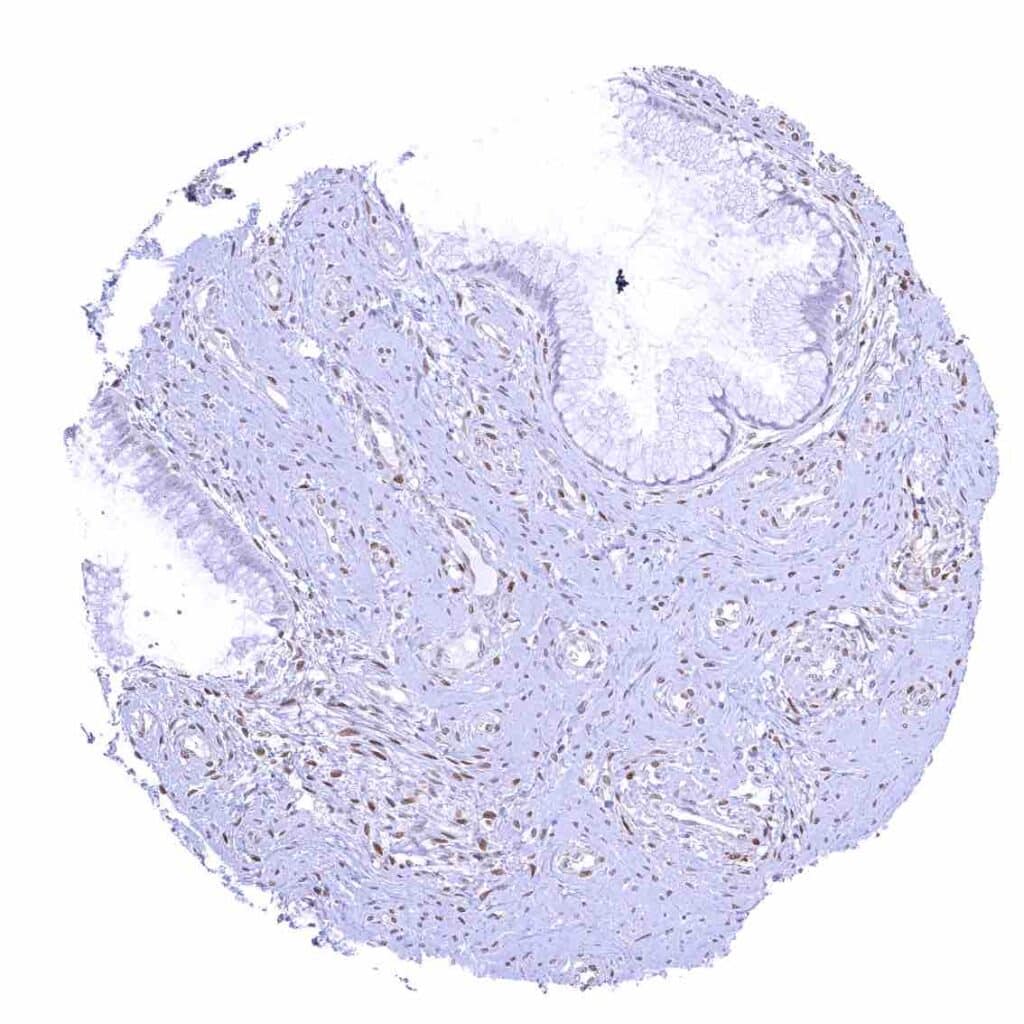

Prostate